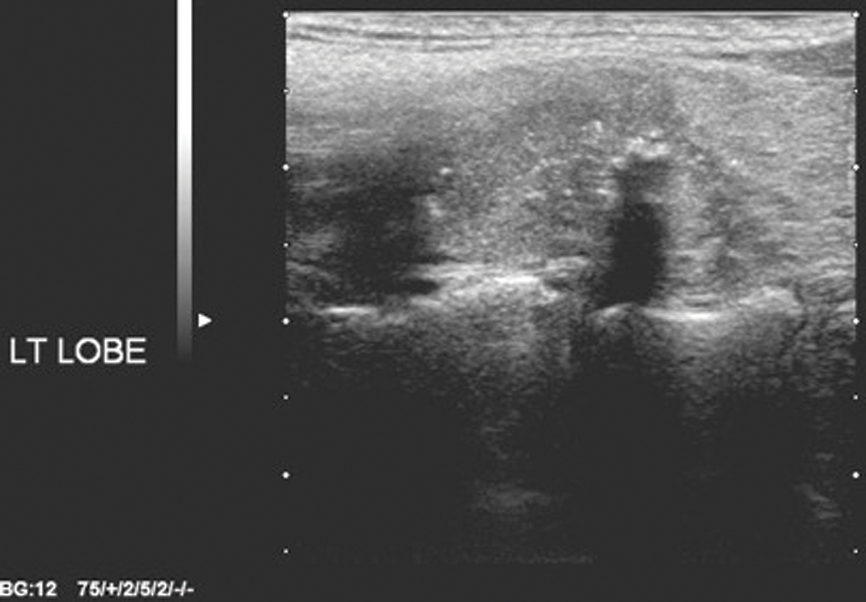

There are a few important points to consider: it is papillary cancer that is accounting for the increase in thyroid cancer incidence, and the four US features used in the Kim and AACE criteria are the cardinal features of papillary cancer (Figures 1-4). For high sensitivity, the Kim Criteria should be used, for high specificity, AACE criteria. The use of nodule size reduces sensitivity and specificity quite markedly.

Figure 3: Microcalcification.